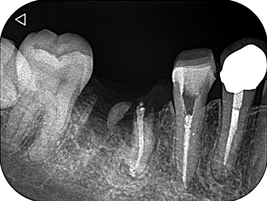

1回法で根管治療を終わらせてデンタルを撮影したところ、目を疑う光景がありました。

「6番の近心根がほぼそのまま残根しているぞ!…どうしよう」

根尖だけ若干残るのなら分かります。しかし、近心根がまるごと残っているのです。

患者さんに残根について説明し、限られたアポイントの中で、なんとか抜歯できました。